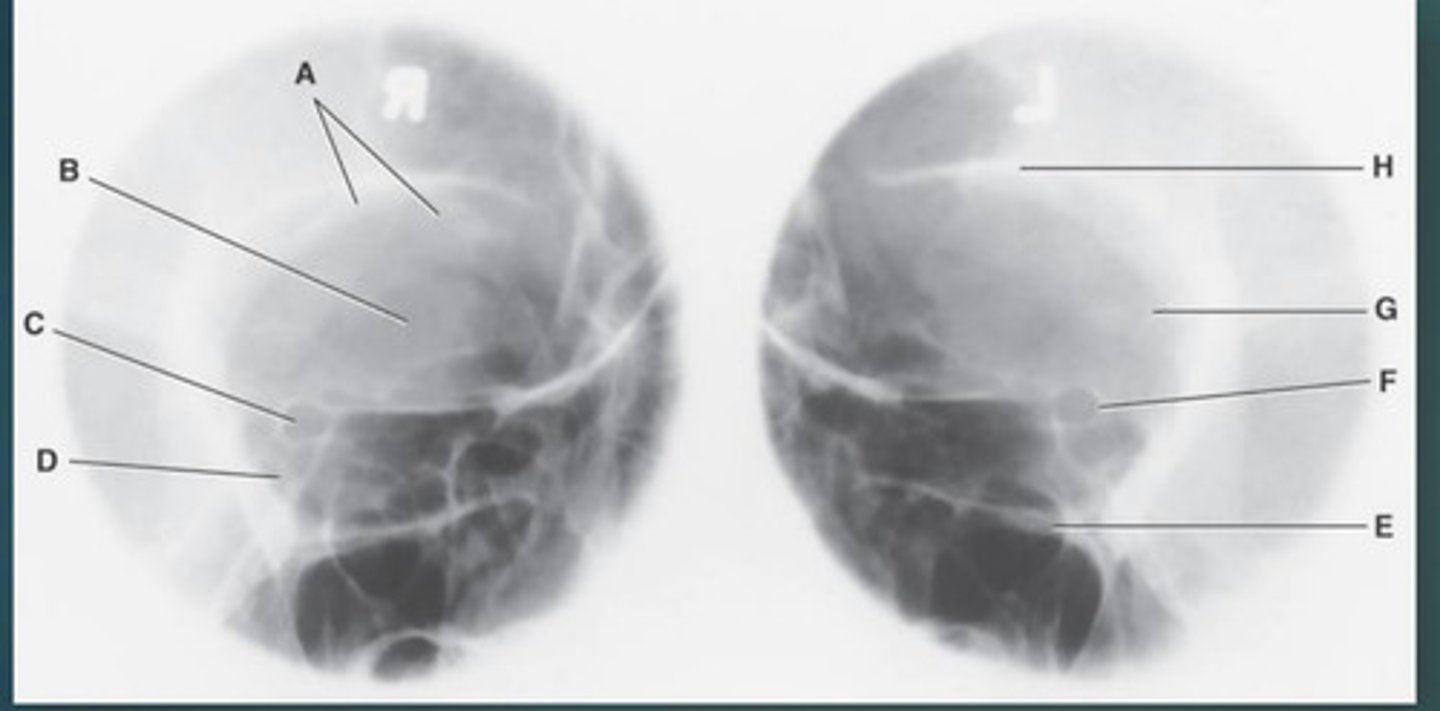

Lateral sinus

What position?

L. Orbital roofs

A.

L. Greater wings of sphenoid

B.

sella turcica of sphenoid

C.

L. Sphenoid sinus

D.

L. Rami of mandible

E.

L. Maxillary sinuses

F.

L. Ethmoid sinuses

G.

L. Frontal sinuses of frontal bone

H.